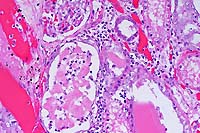

- Case 9-1 . Lung. There are abundant detached and pyknotic

epithelial cells and neutrophils within small and medium caliber

bronchioles.

- Case 9-1 . Lung. Larger bronchioles retain intact

ciliated bronchiolar epithelial cells but scattered foci have

bronchiolar epithelial cells with vacuolation, hypereosinophilia,

pyknosis, loss of cilia, and detachment (degeneration & necrosis).